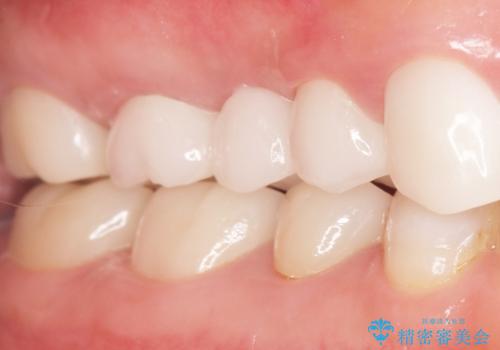

![[ 歯牙破折 ] 違和感のある大臼歯 ブリッジ治療の症例 治療後](https://seimitsushinbi.jp/wp/wp-content/uploads/2021/08/2e4ccba27e1ea02fdacf49749694bbb1-500x350.jpg?v=1629711051)